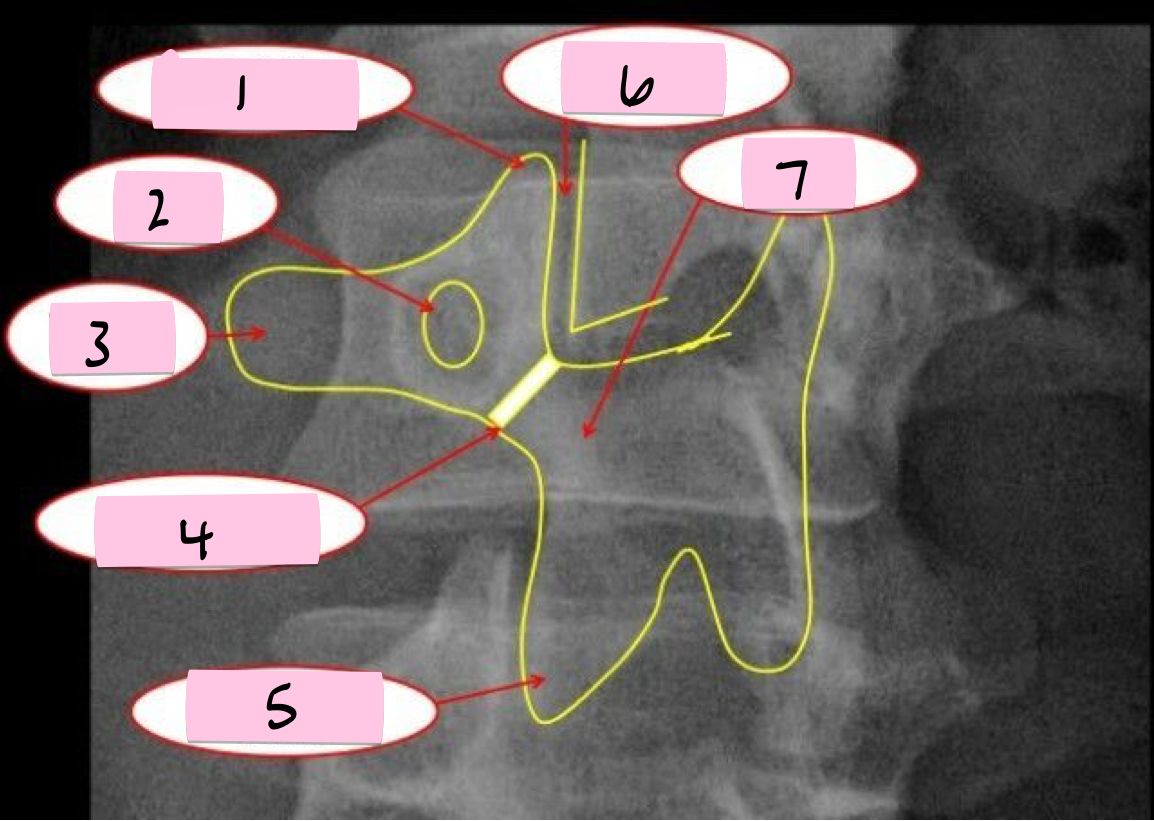

What is 1 pointing to?

Superior articular process

What is 2 pointing to?

Zygapophyseal joint

What is 3 pointing to?

Transverse process

What is 4 pointing to?

Pars interarticularis

What is 5 pointing to?

Inferior articular process

What is 6 pointing to?

Pedicle

What is 7 pointing to?

Scotty dog